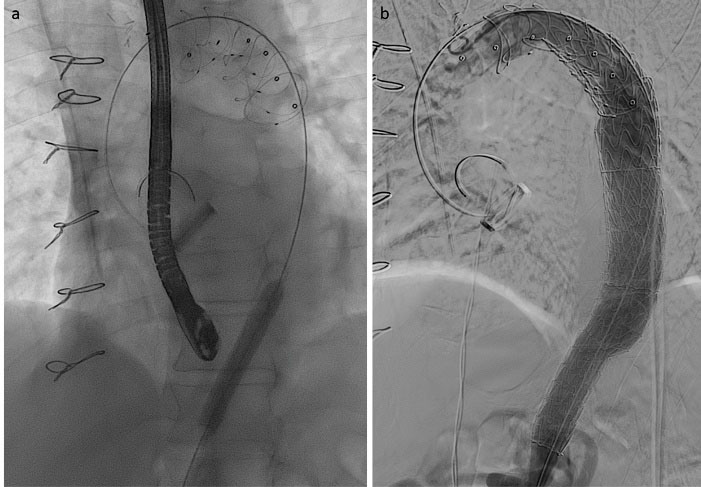

A 56-year-old male, previously operated with mechanical Bentall procedure and right coronary artery bypass grafting for acute type A aortic dissection, was admitted to our hospital with the diagnosis of residual type A chronic aortic dissection to undergo FET procedure. Total arch replacement with FET was performed in operative room (OR) using a 28/30 mm Thoraflex hybrid prosthesis (Vascutek, Inchinnan, UK). Briefly, after circulatory arrest and cerebral protection with selective bilateral antegrade cerebral perfusion at a target nasopharyngeal temperature of 25 °C, the hybrid prosthesis was deployed into the descending thoracic aorta. Distal anastomosis was performed at Ishimaru zone 2 of the aortic arch. Systemic perfusion was re-established through one of the side-branch of the hybrid prosthesis and then, the supra-aortic vessels re-implantation and the proximal anastomosis were completed. The post-operative period was uneventful although the pre-discharged computed tomography angiography (CT) scan control showed the incorrect deployment of the distal endovascular portion of the Thoraflex in the false lumen (). The residual flap length was about 25cm, extending from the middle tract of thoracic aorta to the sub-renal tract; celiac trunk, superior mesenteric artery and right renal artery originated from true lumen, left renal artery from false lumen. Then, the aortic team decided to perform an angiography to evaluate the feasibility to access the false lumen through an intimal tear visualized in the pre-discharged CT examination in the middle portion of the thoracic aorta (), in order to evaluate the possibility to create a communication between the stent graft portion of the Thoraflex in the false lumen and the true lumen. After the angiographic confirmation of the feasibility of the procedure, the patient was then scheduled to perform a thoracic endovascular aortic repair (TEVAR). In a hybrid operative room, with the support of intraoperative transesophageal echo-guidance, the access to the false lumen was through the cannulation of the intimal tear located in the middle tract of the thoracic aorta. Then, the cannulated tear was dilated with the use of balloon catheter (Medtronic Evercross Pta Baloon Catheter, 6x60mm and 8x60mm, Minneapolis, MN) (). After positioning of an ultra-stiff guide wire through the dilated tear, two stent grafts were released proximally (Gore Tag Thoracic Stent Graft 28 mm x 28 mm x 150 mm, Usa AZ) in the portion of the Thoraflex deployed into the false lumen and distally (Gore Tag Thoracic Stent Graft 31 mm x 31 mm x 150 mm, Usa AZ) in the true lumen of thoracic aorta above the celiac trunk (). The intraoperative angiography showed the successful outcome of the procedure (); the postoperative period was uneventful and the patient was discharged in seventh post-procedural day. The pre-discharged CT scan control confirmed the complete exclusion and thrombosis of the false lumen in the thoracic aorta (). The CT scan performed at two years follow-up confirmed the good result of the procedure ().

jcvtr-14-205-g002

Figure 2. Intraoperative cannulation and dilation of the thoracic intimal tear (a) and angioscopy control after deployment of the stent graft (b).